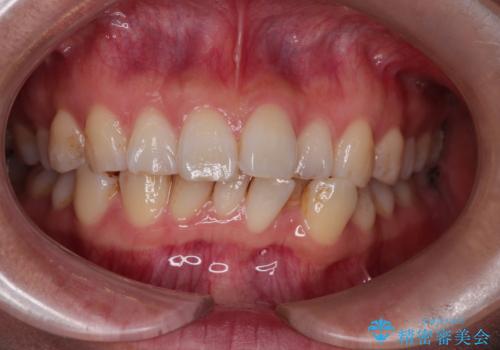

- 凸凹を治したいと来院された患者様です。

インビザラインにて、遠心移動を行いながら綺麗に配列することができました。

側切歯が低位の場合、反対咬合を改善した後に挺出させるのはワイヤーの方が適しています。